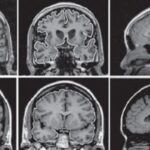

Þó að gervigreind hafi verið staðfest fyrir greiningu á sykursýki, hefur það reynst flóknara að beita henni á gláku, þar sem hún er ekki aðeins ein sjúkdómur heldur samansafn einkenna. Rannsóknin var framkvæmd af vísindamönnum við University College London og Moorfields Eye Hospital, þar sem þeir notuðu 6.304 fundus myndir úr stórri þýði, EPIC-Norfolk Eye Study, til að bera saman nákvæmni gervigreindar og þjálfaðra manna í greiningu á gláku.

Niðurstöðurnar sýndu að gervigreindin greindi rétt 88 til 90 prósent af þeim sem höfðu gláku, á meðan mannlegir greinarar voru réttir 79 til 81 prósent af tímum. Þó að gervigreindin greindi ekki á milli þeirra sem höfðu gláku eða gætu hugsanlega haft hana, var hún prófuð á þýði sem endurspeglar betur raunverulegar aðstæður við venjulega skimun, þar sem aðeins 11 prósent augna í gagnasafninu voru grunaðir um gláku.